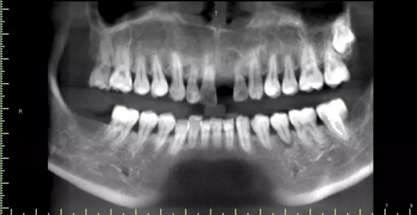

1.術(shù)前CT

2.術(shù)前植體設(shè)計(jì)

術(shù)后CT